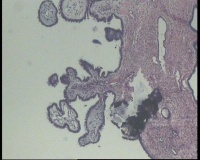

求会诊!左侧卵巢囊肿,够交界性浆液性囊腺瘤吗?

左侧卵巢囊肿大小约6.5x6.0厘米

碎囊壁组织5.0厘米一堆,壁厚0.1—0.4厘米,局灶囊壁见散在赘生物0.3,0.5厘米。另见完整小囊肿1.5x1.0厘米,无内容物,壁厚0.1厘米,内壁附0.8x0.7x0.4厘米赘生物,颗粒状

交界性浆液性乳头状囊腺瘤